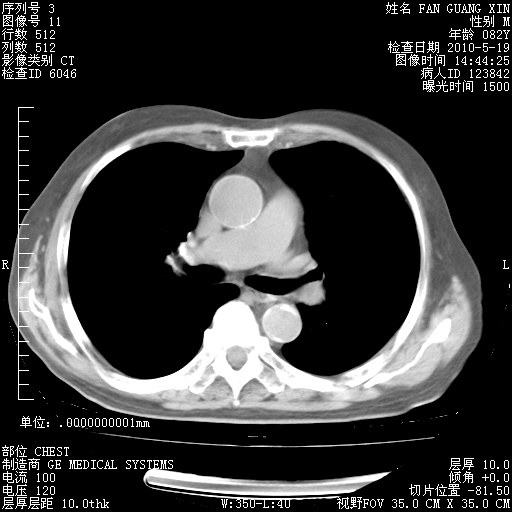

可改为口服强的松40-50mg/d治疗,若病情仍稳定,胸部阴影不再吸收可逐渐减量